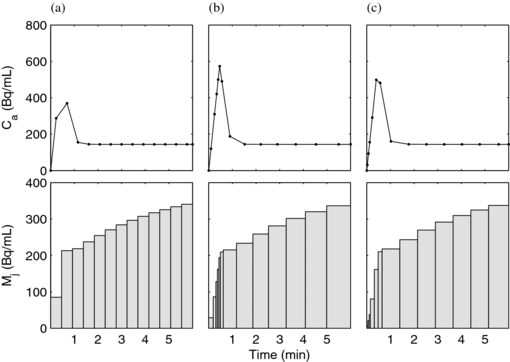

In the first optimization method, the schedule was parameterized as a list of 13 contiguous frame durations. The quantity ![$\left[ {\det ( H )} \right]^{ - 1}$](https://content.cld.iop.org/journals/0031-9155/58/16/5783/revision1/pmb463817ieqn4.gif) was used as the objective function and was minimized using MATLAB's fmincon with an initial guess of uniform (18 s) frames (figure 3(a)) and constrained such that the sum of all frames equalled the 6 min study duration. As expected, the iterative optimization preferred numerous short-duration frames early after the arrival of activity and longer duration frames later, when the curve shape was not changing as rapidly (figure 3(b)). Iterative optimization was feasible with up to 13 frames with careful attention given to initial guesses, tolerances, and other optimization algorithm parameters in order to avoid local minima. Next, we exhaustively searched 13-frame designs following the parameterization method described in section 2.4. The optimal 13-frame schedule from the exhaustive search is shown in figure 3(c); its corresponding det(H) 8.71×1012, slightly lower than the iteratively optimized 13-frame schedule (det(H) = 9.61×1012) shown in figure 3(b). The slightly higher value with iterative optimization is due to the iterative method having access to parameter values between those on the exhaustive method's grid. As expected, both optimization approaches yielded higher values for the objective function, and are therefore expected to provide better estimate precision, than the initial condition (figure 3(a)) with uniform frame durations (det(H) = 2.95×1012).

was used as the objective function and was minimized using MATLAB's fmincon with an initial guess of uniform (18 s) frames (figure 3(a)) and constrained such that the sum of all frames equalled the 6 min study duration. As expected, the iterative optimization preferred numerous short-duration frames early after the arrival of activity and longer duration frames later, when the curve shape was not changing as rapidly (figure 3(b)). Iterative optimization was feasible with up to 13 frames with careful attention given to initial guesses, tolerances, and other optimization algorithm parameters in order to avoid local minima. Next, we exhaustively searched 13-frame designs following the parameterization method described in section 2.4. The optimal 13-frame schedule from the exhaustive search is shown in figure 3(c); its corresponding det(H) 8.71×1012, slightly lower than the iteratively optimized 13-frame schedule (det(H) = 9.61×1012) shown in figure 3(b). The slightly higher value with iterative optimization is due to the iterative method having access to parameter values between those on the exhaustive method's grid. As expected, both optimization approaches yielded higher values for the objective function, and are therefore expected to provide better estimate precision, than the initial condition (figure 3(a)) with uniform frame durations (det(H) = 2.95×1012).

Figure 3. PET TACs with the same parameters shown with 13 frames following uniform spacing (a), optimized iteratively (b) and optimized in an exhaustive search (c). The top row shows the input functions, calculated as a linear interpolation of the PET-sampled LV cavity measurement as would be done with experimental data. The bottom row shows the noise-free PET TACs representing the myocardium region.